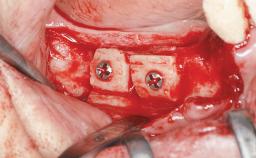

An 18-year-old man was referred for implant therapy in the posterior mandible to the Department of Oral Surgery and Stomatology (University of Bern, Switzerland). He was healthy and did not smoke. Tooth 35 was congenitally missing, involving a single-tooth edentulous space that offered an adequate mesiodistal dimension for implant placement but exhibited a typical pattern of buccal flattening. A panoramic radiograph was obtained, which revealed a sufficient vertical bone height above the mandibular canal and a normal bone structure in the edentulous area.

Bone Augmentation Horizontal|Staged

Augmentation Materials Autogenous chips|Autogenous block(s)|Xenogenous|Membrane

Bone Volume Deficient horizontally, requiring prior grafting